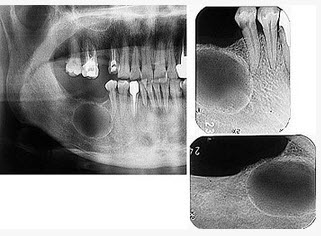

发现下前牙变色,唇侧牙龈一肿物一月余,经X线检查,结果如图。最可能的诊断是()

A、根尖囊肿

B、牙龈瘤

C、根尖脓肿

D、成釉细胞瘤

E、牙骨质瘤

A